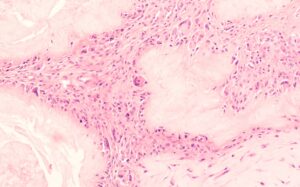

When uric acid levels in the blood become too high, the excess uric acid begins to crystallize. These uric acid crystals often deposit in the joints, particularly the big toe, leading to painful gout attacks. Over time, crystals can also accumulate in the kidneys, increasing the risk of kidney stones and even kidney damage. This crystallization process is one of the main reasons why managing uric acid levels is essential for joint and kidney health.

- Formation of tophi, which are hard deposits of uric acid crystals that appear under the skin around joints.